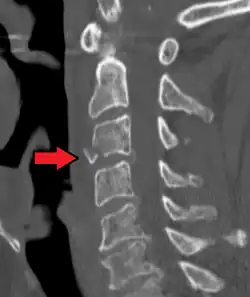

| A fracture of the base of the dens (a part of C2) as seen on CT | |

On CT scan or X-ray, a cervical fracture may be directly visualized. In addition, indirect signs of injury by the vertebral column are incongruities of the vertebral lines,[7] and/or increased thickness of the prevertebral space:[8]

![CT scan of normal congruous vertebral lines[7]](./_assets_/Vertebral_lines.png)